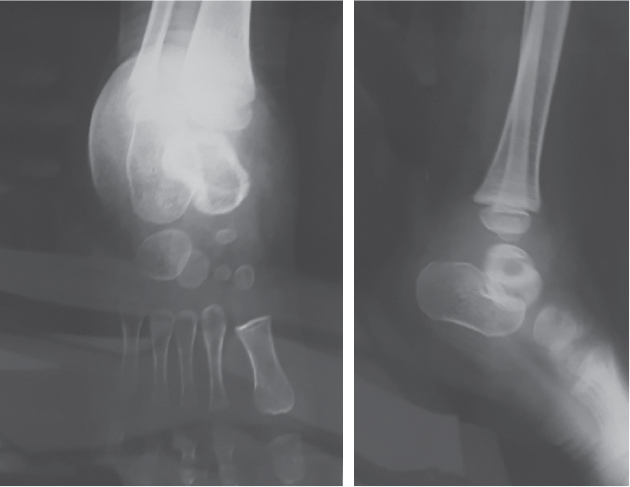

unreactive. X-ray showed osteolytic lesion in talus with breach in dorsal

cortex (Fig. 2). On needle aspiration from talus, we found sanguineous fluid.

Figure 2. X-ray anteroposterior and lateral view showing

a lytic lesion involving the talus.